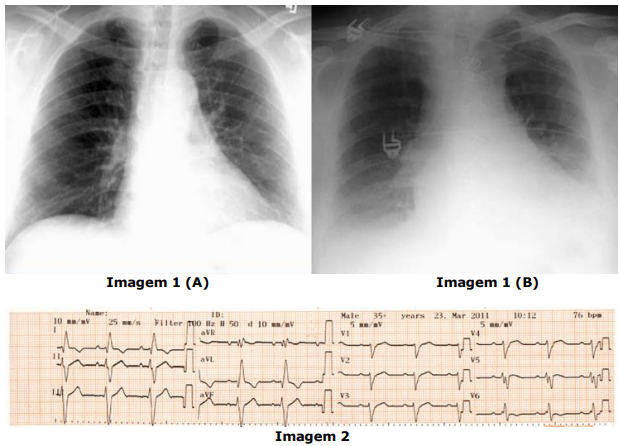

( ) A imagem 1 (A) é de um raio-X em projeção posteroanterior (PA) e é a projeção mais adequada para a avaliação do átrio esquerdo e ventrículo direito.

( ) A imagem 1 (B) é de um raio-X em projeção anteroposterior (AP) e é a projeção mais adequada para a avaliação do ventrículo esquerdo.

( ) A velocidade de registro no eletrocardiograma da imagem 2 é de 50 mm/s.

( ) A amplitude do eletrocardiograma da imagem 2 é de 10 mm/mV.

( ) No eletrocardiograma da imagem 2, a onda P é positiva em DII e aVF e negativa em aVR, sugerindo origem a partir do nó sinusal.